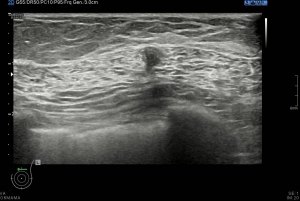

Los vientres anteriores de los Músculos Digástricos derecho e izquierdo forman los bordes laterales del triángulo submentoniano, mira:

En este triángulo lo que vas a encontrar son ganglios.

Los vientres anteriores de los músculos Digástricos, que son el objeto del desarrollo de este Post, son dos estructuras musculares redondeadas en el corte transversal, imagen 1, y alargados si los estudiamos en el eje largo, imagen 3, mira:

Ecográficamente los músculos digástricos en eje corto tienen semiología hipoecogénica, en aspecto de noche estrellada, como la de hoy, y en el eje largo en forma de penacho o en forma de plumas con las fibras alargadas y paralelas a la superficie.